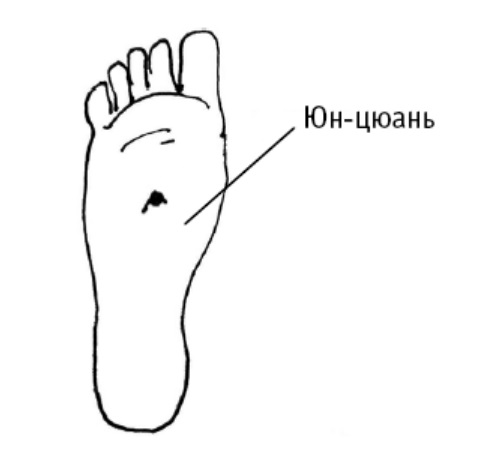

Юн-цюань («бурлящий источник, родник») расположена в середине подошвы, между 2-й и 3-й плюсневыми костями, в углублении, образующемся при поджатии пальцев стопы (в углублении в середине подошвы).

Дополнительный эффект от воздействия на юн-цюань: точку используют в критических состояниях (отравление, судороги); при ломоте в пояснице и коленях, головной боли, головокружении, шуме в ушах, бессоннице, сердцебиение, снижении памяти, нарушении мочеиспускания; при кашле, сухости во рту и в горле, нервных болезнях и многих других.

Для борьбы с дистонией надавливают на точки Юн-цюань, расположенные на ступнях. Обхватите рукой ступню и давите на точку большим пальцем, прилагая среднее усилие. Проделывайте процедуру утром и вечером для каждой ступни.

Юн-цюань («бурлящий источник, родник») расположена в середине подошвы, между 2-й и 3-й плюсневыми костями, в углублении, образующемся при поджатии пальцев стопы (в углублении в середине подошвы).

Дополнительный эффект от воздействия на юн-цюань: точку используют в критических состояниях (отравление, судороги); при ломоте в пояснице и коленях, головной боли, головокружении, шуме в ушах, бессоннице, сердцебиение, снижении памяти, нарушении мочеиспускания; при кашле, сухости во рту и в горле, нервных болезнях и многих других.

Для борьбы с дистонией надавливают на точки Юн-цюань, расположенные на ступнях. Обхватите рукой ступню и давите на точку большим пальцем, прилагая среднее усилие. Проделывайте процедуру утром и вечером для каждой ступни.